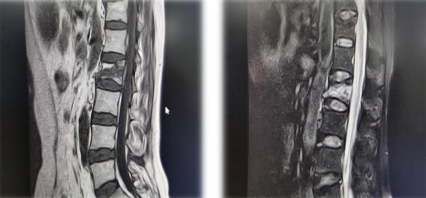

患者L2椎体骨质疏松性压缩性骨折

MRI

脊柱科孟磊副主任医师给老人仔细检查,老人L2椎体骨质疏松性压缩性骨折,需要进行PKP(经皮椎体后凸成形术)。